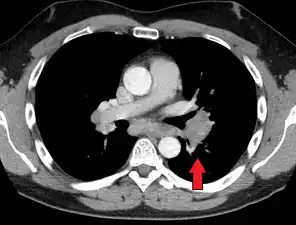

Hilar adenopathy especially on the person's left (transverse CT)

Chest radiograph changes are divided into four stages:[105]

- bihilar lymphadenopathy

- bihilar lymphadenopathy and reticulonodular infiltrates

- bilateral pulmonary infiltrates

- fibrocystic sarcoidosis typically with upward hilar retraction, cystic and bullous changes

Although people with stage 1 radiographs tend to have the acute or subacute, reversible form of the disease, those with stages 2 and 3 often have the chronic, progressive disease; these patterns do not represent consecutive "stages" of sarcoidosis. Thus, except for epidemiologic purposes, this categorization is mostly of historic interest.[28]